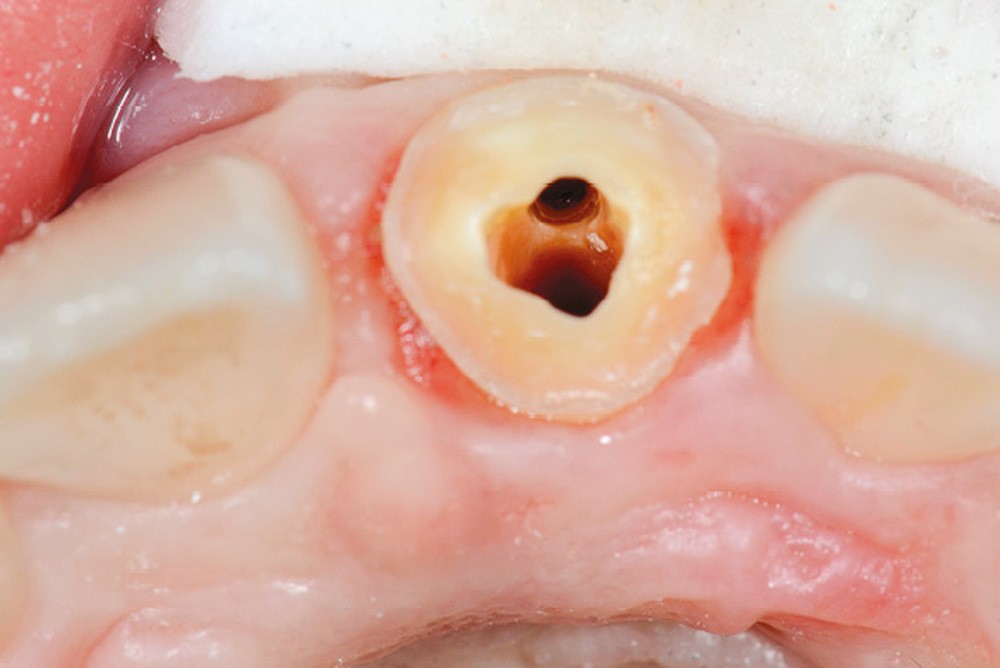

Une patiente de 18 ans, sans antécédents médicaux, se présente en consultation pour des douleurs à la pression au niveau de la 21. Cette dent a subi quelques mois auparavant un choc violent, qui a nécessité un traitement endodontique en urgence et la réalisation d’une couronne transitoire. L’examen clinique révèle une couronne transitoire à tenon (fig. 1 et 2).

La dépose de la couronne transitoire et du tenon métallique scellé confirme la présence d’un faux canal. Dès ce stade, le choix de la RCR amène une réflexion thérapeutique et s’intéresse à différents paramètres.

Dans le cas présent, la structure résiduelle est évaluée à 2 parois vestibulaire et distale d’environ 2 mm de hauteur, les autres mesurant environ 1 mm : le choix d’une RMIPP est possible, sous réserve de pouvoir réaliser la mise en place d’un champ opératoire.